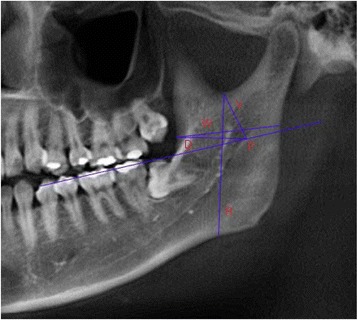

To compare the anterior and posterior positions of mandibular foramen, the distance (D, in mm) between ‘a’ and the MF and the shortest distance (W, in mm) between ‘a’ and the posterior border of mandibular ramus were measured. To compare the vertical position of the mandibular foramen, the length (V, in mm) between ‘s’ and the MF and the length of the perpendicular line (P, in mm) from the extension of occlusal plane to the MF and the shortest distance (R, in mm) between ‘s’ and the inferior edge of the mandible was measured (Table 2, Fig. 2).

Items of measurement

| W | Diameter of ramus |

| D | Distance of MF from a |

| V | Distance of MF from s |

| P | Distance of MF from l |

| R | Distance of Mandibular lower border from s |

Fig. 2.

Items of measurement